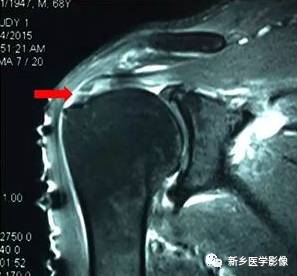

病例四:

红色箭头:肩胛下肌腱损伤

黄色箭头:肱二头肌长头腱(在位)